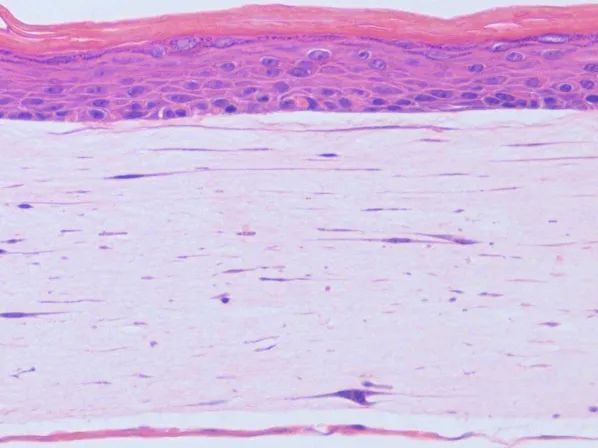

在肿瘤相关领域,赛箔与合作者共同研发基于生物3D打印技术构建的肿瘤微组织(PDT),涵盖十余个癌种,包括高发肿瘤、难治肿瘤、妇科肿瘤和儿童肿瘤,培养成功率超过了90%。通过近千例样本研究,证实PDT与患者组织具有高度一致的分子特征和药物敏感性,1-2周即可获得准确的药敏检测结果,为治疗赢取宝贵时间,并且可为新药研发企业提供药效评价、入组标准建立、适应症筛选等服务。在再生相关领域,赛箔已建立多种3D组织工程皮肤,包括表皮模型、全层皮肤模型、黑素皮肤模型等,并相应开发多种体外功效测试方法。

黑色素皮肤模型

全层皮肤模型

表皮模型